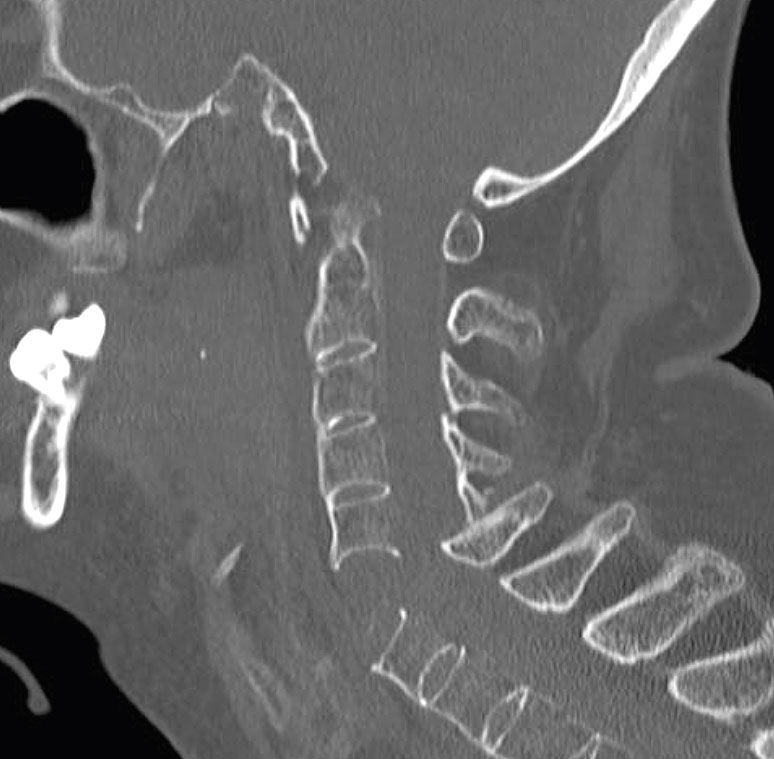

Lokalisation av densfrakturer. Typ 1: genom toppen av dens. Typ 2: genom basen av dens. Typ 3: genom dens och ner i C2.

Datortomografi av traumatisk densfraktur med dislokation, typ 2.